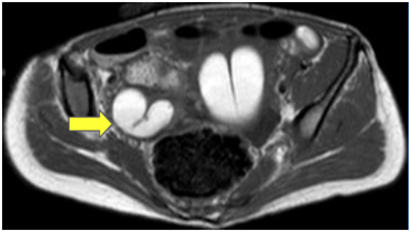

The MRI revealed bilateral ureteropelvic calyceal ectasia, an enlarged uterus with endometrial cavity distension and the presence of a septum, a 22mm hematometra, with no recognizable external cervix (Figure 2A). The vagina was not visible (Figures 2B, 2C, 2D, and 2E). Other findings included dilated Fallopian tubes (hematosalpinx), normal bilateral ovaries, and superficial endometriosis.

Figure 2. Magnetic Resonance Imaging (RMI)

Figures 2C, 2D, 2E: Both adnexal regions show hematosalpinx (39 x 27 mm on the right and 47 x 26 mm on the left). Ovaries appear normal, and there is thickening of the peritoneal tissue, likely superficial endometriosis.